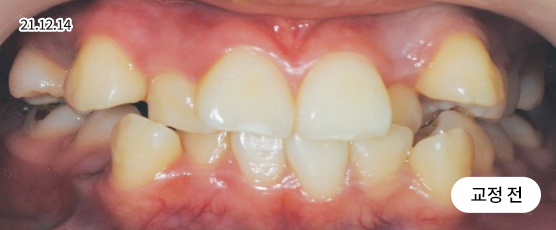

덧니교정 Solution

덧니는 악궁 크기, 얼굴형, 골격 등을 고려해 발치, 비발치를 현명하게 판단하여 치료합니다.

치아가 정렬될 공간을 확보하기 위해, 경우에 따라 소구치(작은 어금니)를 발치할 수 있습니다.

* 본 사진은 동일 조건에서 촬영되었으며, 환자 본인의 동의를 얻어 게재되었습니다.